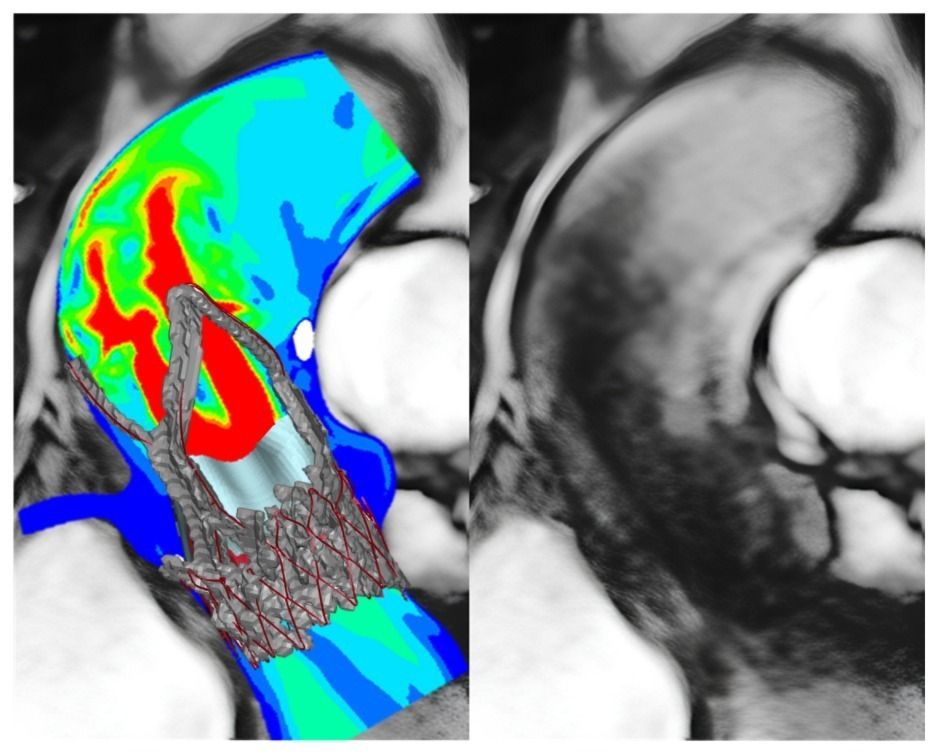

Foto e video